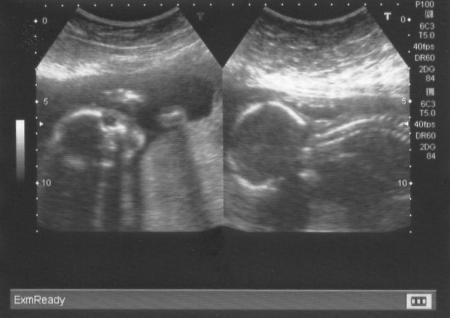

klar hab ich auch Bilder bekommen.... :0)

Einmal das Gesichtchen und einmal den Körper.